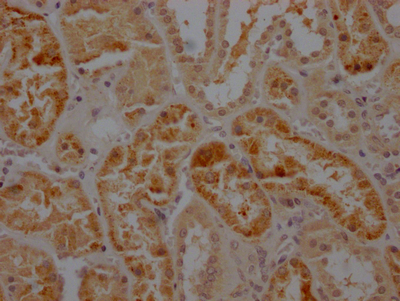

• IHC image of CSB-RA782200A0HU diluted at 1:100 and staining in paraffin-embedded human lung cancer performed on a Leica BondTM system. After dewaxing and hydration, antigen retrieval was mediated by high pressure in a citrate buffer (pH 6.0). Section was blocked with 10% normal goat serum 30min at RT. Then primary antibody (1% BSA) was incubated at 4℃ overnight. The primary is detected by a Goat anti-rabbit IgG polymer labeled by HRP and visualized using 0.05% DAB.

• IHC image of CSB-RA782200A0HU diluted at 1:100 and staining in paraffin-embedded human kidney tissue performed on a Leica BondTM system. After dewaxing and hydration, antigen retrieval was mediated by high pressure in a citrate buffer (pH 6.0). Section was blocked with 10% normal goat serum 30min at RT. Then primary antibody (1% BSA) was incubated at 4℃ overnight. The primary is detected by a Goat anti-rabbit IgG polymer labeled by HRP and visualized using 0.05% DAB.